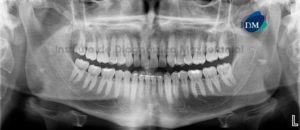

Paciente masculino de 20 años acude al Instituto de Diagnóstico Maxilofacial para evaluación imagenológica a nivel maxilofacial. A la evaluación de la radiografía panorámica se